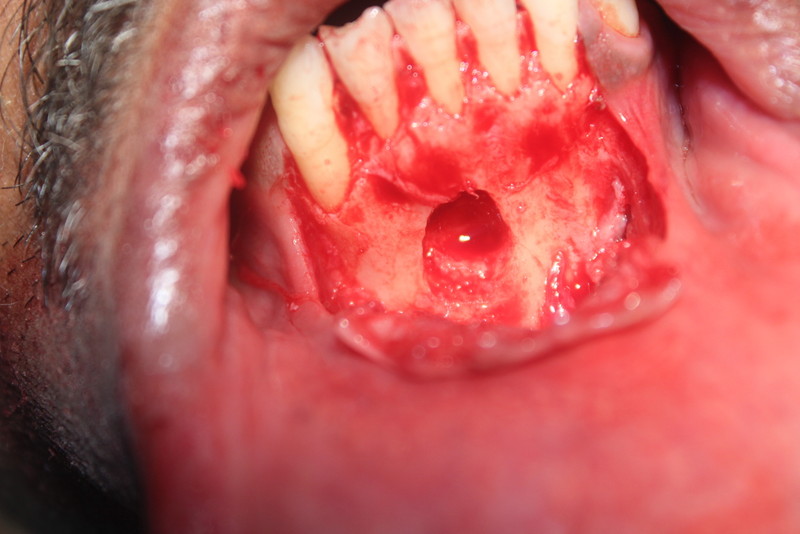

Apicoectomy